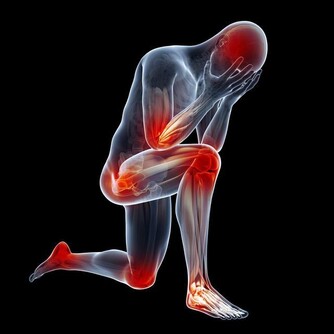

主要症有:屈伸活動受限,局部有明顯壓痛或腫脹,

疼痛可反射至胸背下部、下腹部、上臀部、兩側大腿前面、外側或後面直至踝部,

同時因天氣變化,甚至病狀加重。

醫學家認為風濕、腎虛、損傷是導致腰痛的主要因素。